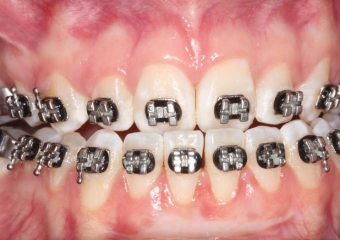

Mordida inicial

Mordida após a cirurgia